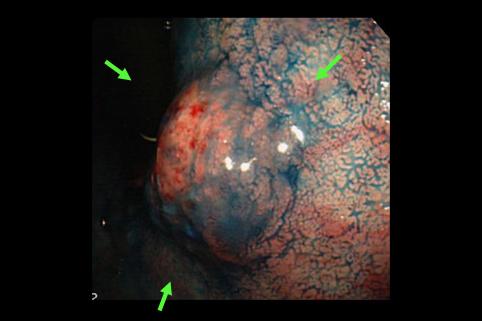

疾病(病理主体)的分类恶性上皮性肿瘤/粘液癌

部位(按器官分)胃(部位)/体部

检查方法内窥镜

肿瘤的肉眼分类0型(表在型)/I型(I)

肿瘤最大直径25~29

肿瘤的深度sm